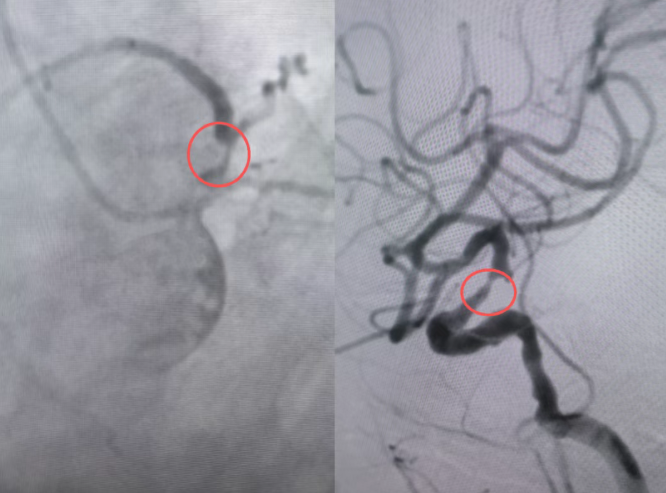

手术当天,介入导管室内展开了一场紧张有序的“协同战”。心内科隋立有副院长团队率先攻坚,精准地将一枚支架送入严重狭窄的冠状动脉,血管管腔即刻恢复血流,心脏供血问题得到解决,为后续脑部治疗扫清了最大障碍。麻醉科团队凭借丰富经验,精准用药,全程维持患者脆弱的心脑血管功能稳定。随后,神经内科III病区姜福成主任团队接力续战,通过脑血管介入手段,成功开通了堵塞的脑血管,恢复了大脑供血。

整个手术过程中,三大团队无缝衔接,通过一个血管入口,针对不同部位的“病灶”发起总攻。患者心脑两大隐患被一次性顺利拆除,术后生命体征平稳,转入监护室进行后续康复。